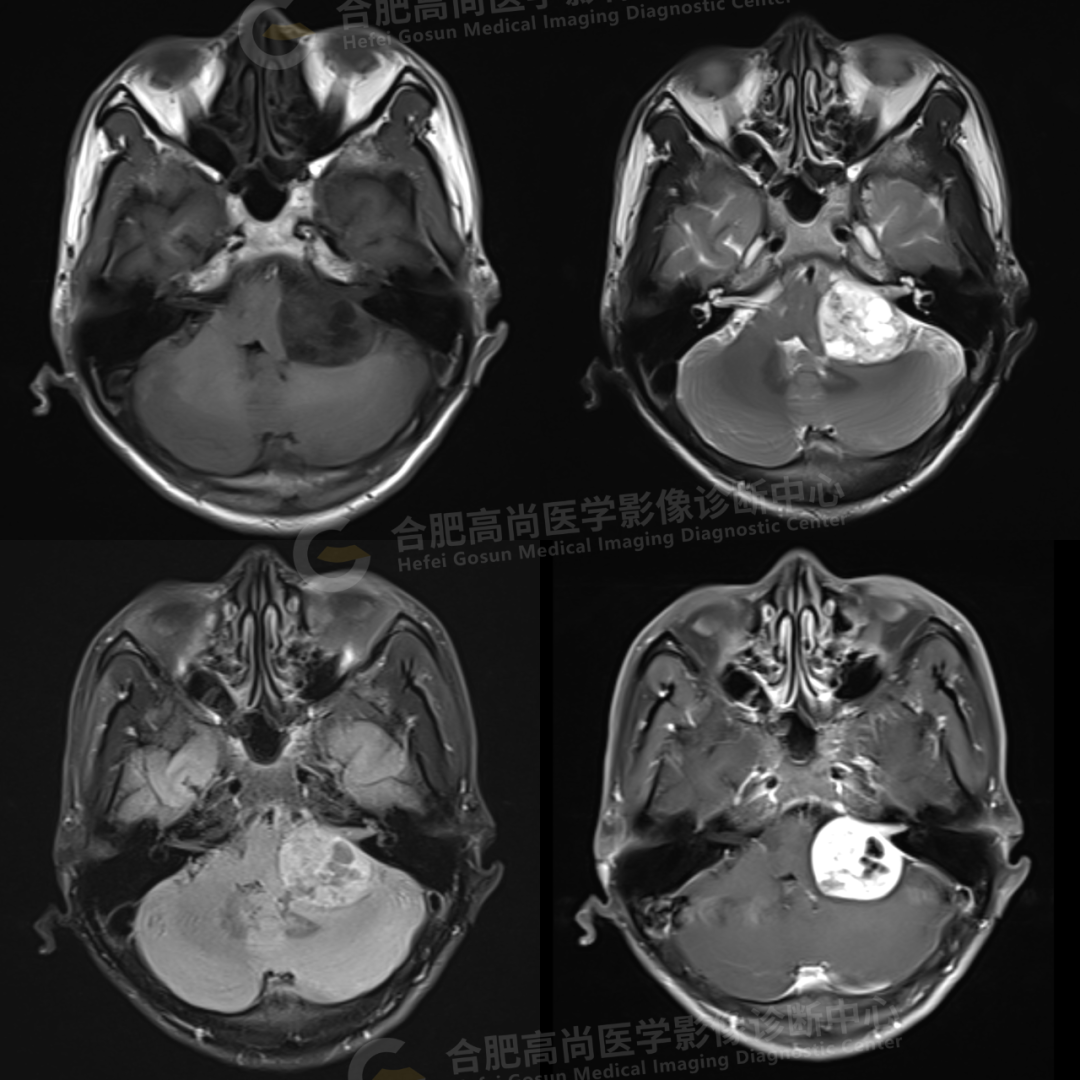

2、颅脑 MRI

颅脑 MRI 平扫+增强显示:左侧桥小脑角区可见类圆形囊实性异常信号,呈长 T1 长 T2 信号,flair 序列呈混杂高信号,内可见坏死囊变,大小约 3.0*3.5 cm,边界清晰,增强后病灶实性成分明显强化,囊变区未见明显强化,左侧内听道扩大,听神经增粗伴明显强化,病灶邻近小脑及桥脑受压推移变形,四脑室变形变窄,对侧桥小脑角区未见异常。

结论:左侧桥小脑角区占位,考虑听神经瘤。

(二)MRI 表现:

肿瘤主体在桥小脑角区,见内听道扩大,听神经增粗为特征,肿瘤形态大多数呈类圆形,边缘光滑,这与肿瘤大多数有包膜有关,包膜在 T1WI 与 T2WI 均为低信号。部分肿瘤不规则形,瘤体较大时,可压迫邻近结构,使脑干、小脑受压,造成第四脑室受压变形。

听神经瘤一般呈实性,囊实性和囊性三种:

(1)实性:TlWI 呈低或稍低信号,T2WI 呈高或稍高信号。

(2)囊性:则呈长 T1 长 T2 信号。增强扫描呈均匀或不均匀强化。

(3)囊实性:T1WI 呈低及稍低信号,T2WI 呈高及稍高信号。